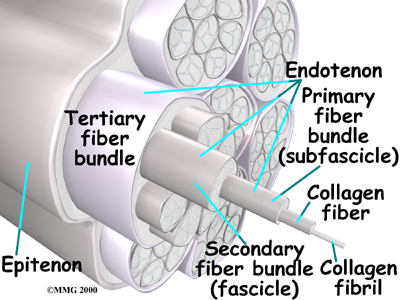

A ligament is made up of , similar to a nylon rope. A sprain results in stretching or tearing of the ligaments. Minor sprains only stretch the ligament. A tear may be either a complete tear of all the strands of the ligament or a partial tear of only some of the strands. The ligament is weakened by the injury; how much it is weakened depends on the degree of the sprain.